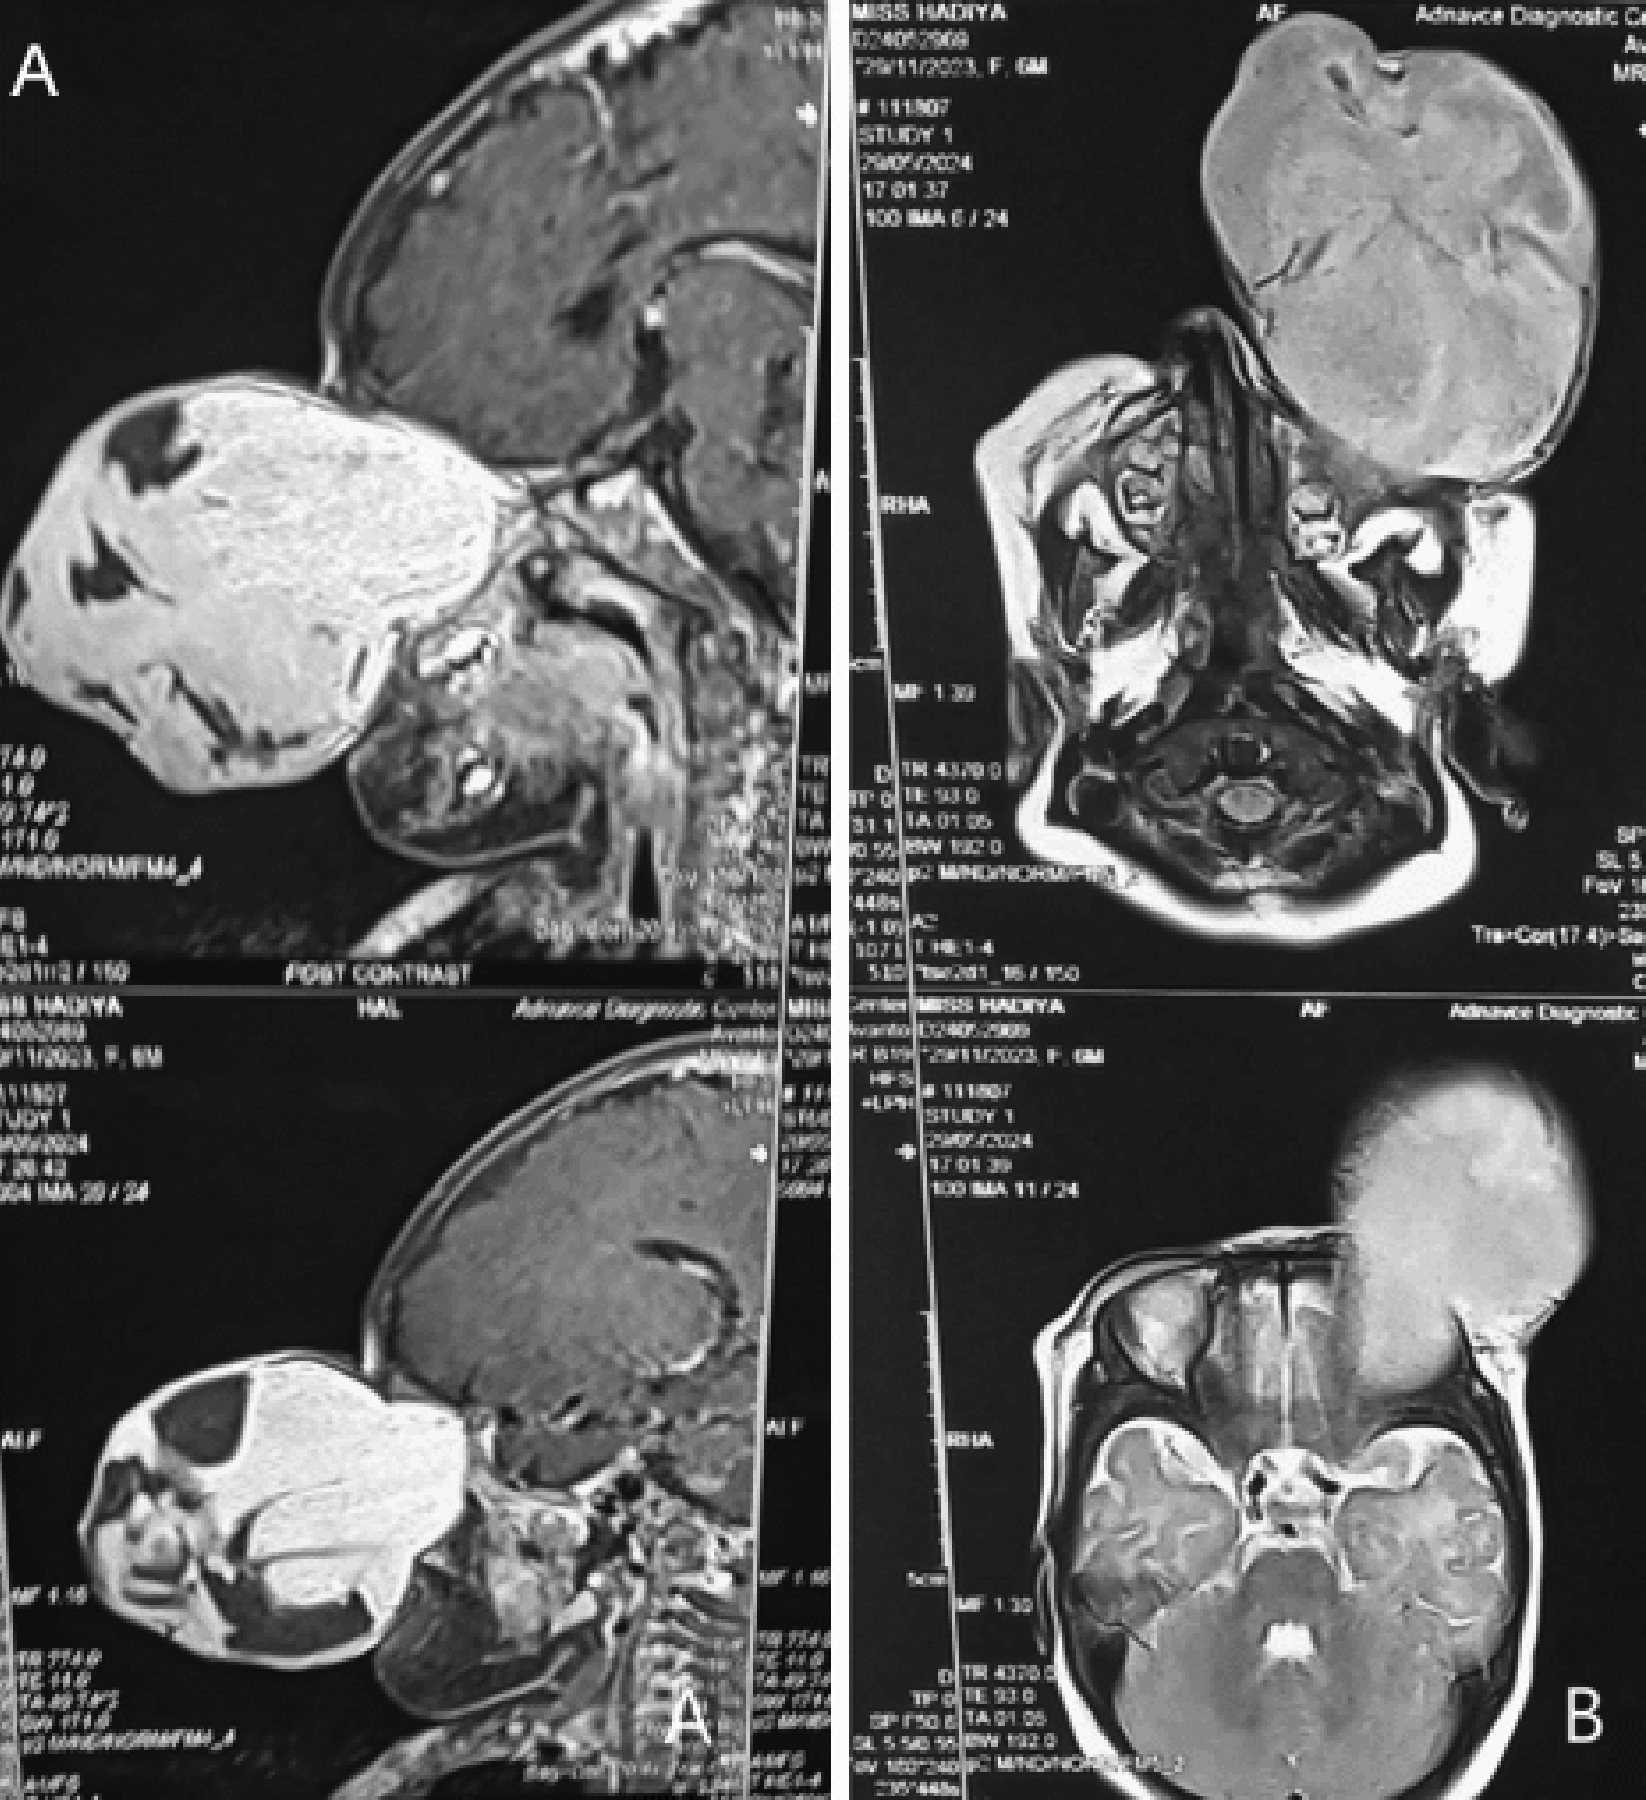

On general physical examination, the child was pale-looking, irritable, and restless. Pre-auricular, post-auricular, submandi-bular, and supraclavicular lymph nodes were not palpable. Imaging techniques revealed an intraconal mass that was extending up to the orbital apex, involving extraocular muscles but not eroding the orbital walls (Figure 2). Pre-auricular, post- auricular, submandibular, and cervical lymph nodes were not palpable. Surgical decompression with total exenteration of the left eye was carried out under general anaesthesia (Figure 1D). A histopathological report revealed a small round-cell undifferentiated sarcoma. Grossly, the tumour mass weighed about 280 grams.

Figure 2: MRI sagittal view and axial views of howling hyper intense lesion extending up to the left orbital apex.